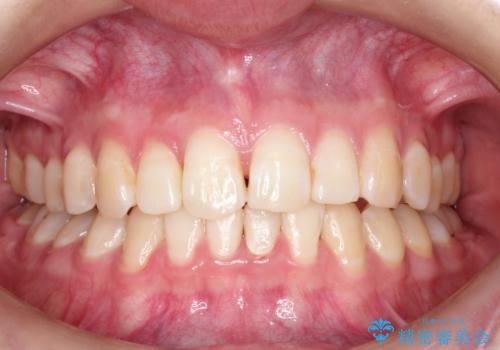

ハーフリンガル ワイヤー矯正による非抜歯・過蓋咬合の治療

- 20代女性

- 非抜歯、大臼歯遠心移動による臼歯関係の是正・過蓋の改善をハーフリンガル・ワイヤー矯正にて計画した。

現在過蓋咬合の非抜歯治療はマウスピースで行うのが第1選択といっても過言ではありません。